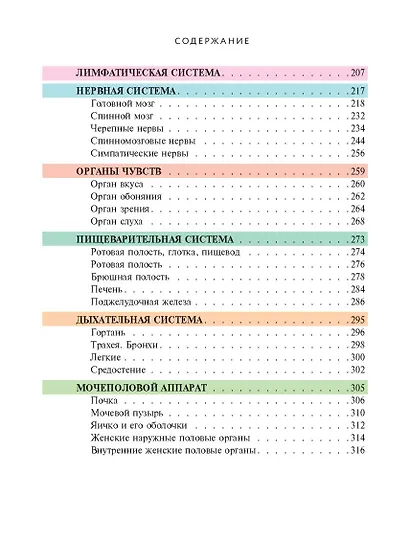

«Популярный атлас анатомии человека» — это оптимальный объем базовых знаний о строении человеческого тела. Созданная современными учеными-анатомами с использованием новейших данных, книга предлагает четко структурированную информацию, изложенную в 10 тематических главах по основным анатомическим системам.

Особую ценность изданию придают высококачественные репродукции классических гравюр из знаменитой «Gray's Anatomy» — самого известного англоязычного учебника по анатомии человека. Более 200 классических иллюстраций выполнены с безупречной детализацией благодаря современным полиграфическим технологиям. Винтажные гравюры XIX века сочетаются с удобным компактным форматом и ярким дизайном, что делает книгу одновременно эстетически привлекательной и практичной в использовании.

"Популярный атлас анатомии человека" — это доступное, красочное и информативное издание, содержащее основные сведения о строении человеческого тела. Написанный ведущими учёными-анатомами с учётом последних научных данных, атлас предлагает систематизированную информацию, разделённую на 10 глав по ключевым анатомическим системам. Книга сочетает в себе ясность изложения и высокое качество визуального материала: она проиллюстрирована классическими гравюрами из знаменитой "Анатомии Грея", что делает изучение анатомии наглядным и увлекательным. Удобный компактный формат практичен в использовании,а цветная печать изображений обеспечивает комфортное чтение и детальное рассмотрение иллюстраций из всемирно известного медицинского учебника.